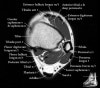

발목 관절의 MRI 단면 영상

- Axial section

Axial PD fat suppression evaluates the tendons and ligaments of the ankle particularly after acute/subacute injuries. It also is sensitive to talar dome osteochondral defects. Alternatively, a T2 sequence can be used to eliminate magic angle artifact that may occur as the tendons travel around the malleolar turns.

Tibiofibular ligaments

-

Lateral ankle ligaments

Deltoid and spling ligaments

Tendon(Achilles, Medial, Lateral, Anterior)